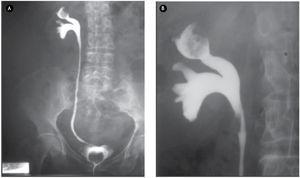

Ante este hallazgo se realizó urografía excretora, en la cual se observó en la fase de eliminación a los 30 minutos defecto de llenado en cáliz superior, sin dilatación de sistemas colectores del lado derecho. En el izquierdo no se aprecia captación de medio de contraste, incluso a los 60 minutos (Figura 1).

Figura 1. Urograma excretor en fase de vaciamiento, donde se observa defecto de llenado en cáliz superior y ausencia de captación del medio de contraste del riñón izquierdo.